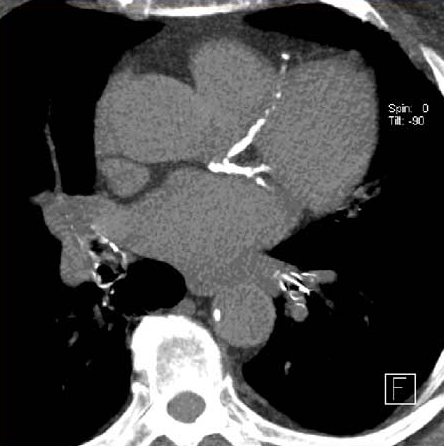

Importancia pronóstica de la determinación del calcio coronario en la TC de tórax para el rastreo de cáncer de pulmón

En las personas que se sometieron a una TC de tórax de baja dosis para la detección del cáncer de pulmón, la presencia de calcio en la arteria coronaria fue un predictor independiente de muerte por cualquier causa y eventos cardiovasculares, incluso después del ajuste por muerte no cardiovascular. Canadian Medical Association Journal, 2 de diciembre de 2024.